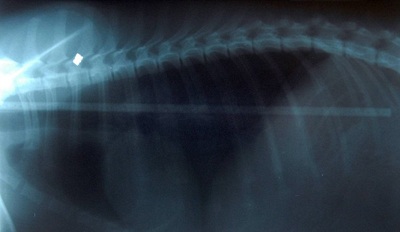

Y tá Laura Lamb nói: “Khu chụp X-quang, các bác sĩ thú y không thể tin vào mắt của mình. Một chiếc gậy dài đến nửa mét chạy từ cổ họng đến cuối thành ruột của Pip. Thật may mắn, chiếc gậy này không làm tổn hại đến nội tạng và con chó đã hồi phục sau phẫu thuật.”

Chiếc gậy dài đến nửa mét chạy từ cổ họng đến cuối thành ruột Pip.

Ảnh chụp X-quang.